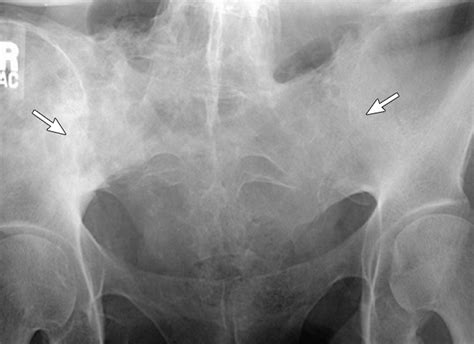

In some cases, an Xray Si Joint may be recommended to confirm the diagnosis and rule out other potential causes of pain. This imaging technique provides detailed images of the joint and can help identify any abnormalities or degenerative changes.